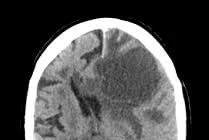

Di căn não là một biến chứng thường gặp trong nhiều loại ung thư, nhưng đặc biệt phổ biến ở những bệnh nhân bị ung thư phổi. Khoảng 15 - 20% bệnh nhân ung thư phổi phát triển di căn não. Tỷ lệ di căn não não cao hơn ở ở bệnh nhân có đột biến gene EGFR và tái sắp xếp ALK, trong đó 50 - 60% di căn não trong quá trình bệnh.